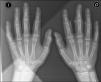

A 14-year-old male, with no history of interest, consulting with a year's history of deformity and symmetrical pattern swelling on the lateral face of the proximal interphalangeal joints (IPJ) of the second, third and fourth fingers, with predominance in the right hand (Fig. 1A and B). He reported no pain, limitation or other associated skin or systemic manifestations.

Analysis, which included complete blood count, biochemistry, coagulation, erythrocyte sedimentation rate, C reactive protein, HLA-B27, rheumatoid factor and antinuclear antibodies, was normal or negative. Plain X-ray showed an increase in soft tissue on the second, third and fourth IPJ of the right hand, with no signs of associated joint or bone involvement (Fig. 2). Magnetic resonance imaging showed oedema and increased soft tissue on the second, third and fourth fingers of the right hand. There were no signs of synovitis or associated collections (Fig. 3). A skin biopsy was performed that revealed compact hyperkeratosis and thickening of the dermis, with an increase in the number of collagen fibres and fibroblasts.